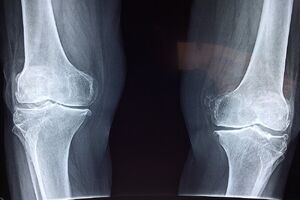

توصیههای طب ایرانی برای جلوگیری از پوکی استخوان

به گزارش مشرق، دکتر سید مهدی میرغضنفری - معاون تعالی دفتر طب ایرانی و مکمل وزارت بهداشت با اشاره به شیوع پوکی استخوان خصوصا در سنین بالا، نگاه طب ایرانی به این بیماری را تشریح کرد و گفت: از دیدگاه مشترک طب ایرانی و فیزیولوژی مدرن، استخوان یک بافت زنده و پویا است که همواره در حال تخریب و بازسازی است و برای حفظ سلامت آن، ضروری است که از طریق جریان خون، غذای باکیفیت و مناسبی دریافت کند.

وی تاکید کرد: اگر خون کیفیت لازم را نداشته باشد، تغذیه مناسبی برای استخوان صورت نمیگیرد و مواد ضروری برای رشد و بازسازی به آن نمیرسد. در نتیجه استخوان بهتدریج ضعیفتر میشود که به این حالت اصطلاحاً پوکی استخوان گفته میشود.